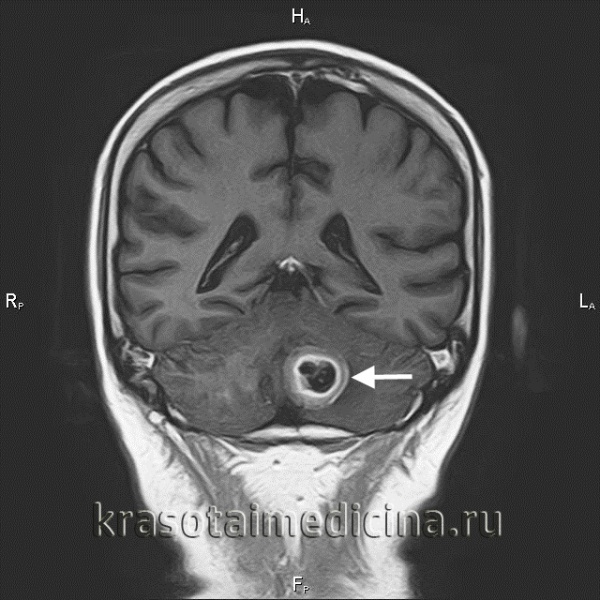

г) Диагностика. Одним из основных компонентов диагностических процедур является нейровизуализация. Метастазы могут показывать повышение сигнала различной интенсивности, а при централизованном некротическом компоненте имитировать глиобластомы. Разнородность структуры — характерный показатель для метастазов. Обязательным исследованием на сегодня является МРТ, в частности, для получения информации о степени заболевания, которое может быть уже неизлечимым на момент постановки диагноза при выявлении десятка или более очагов.

Менингеальный карциноматоз у пациента с доказанным метастазом бронхиальной аденокарциномы. Кистозный, с центральной гиподенсной зоной метастаз рака молочной железы, который может быть принят за глиобластому.. Метахронные метастазы колоректального рака с сопутствующими крупными и мелкими очагами. Аденокарцинома легких с кистозным симптоматическим метастазом в правой височной доле, выявленным на КТ (вверху слева), а также МРТ (вверху справа).

Инфратенториальный очаг гораздо лучше визуализируется на МРТ. Метастаз в пинеальную область с угрожающей окклюзионной гидроцефалией